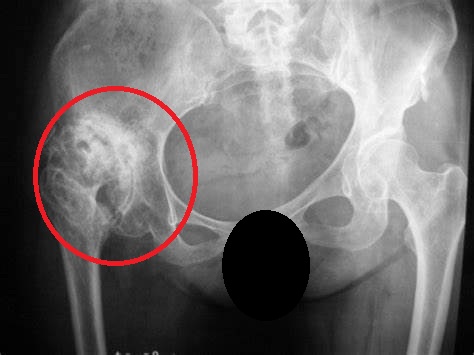

如果头还是圆的,但是股骨头里面可以看到坏死灶的话(如下图),那么这种病人可以尝试保髋手术。

目前来说保髋手术众多,但确切能减轻缓解疼痛症状的无非于股骨头钻孔减压手术了,这个手术通过小切口(相比髋关节置换来说)打钉到患者的股骨头坏死的病灶处,将股骨头局部增加的压力通过钉道释放出来,术后患者疼痛常常可以好转。

但请记住一点,钻孔减压的手术,仅仅适用于股骨头形态良好,用于延缓关节置换年限的手术,后期股骨头坏死也可能进一步加重,导致股骨头变扁塌陷需要置换的,但能延缓一年是一年咯!